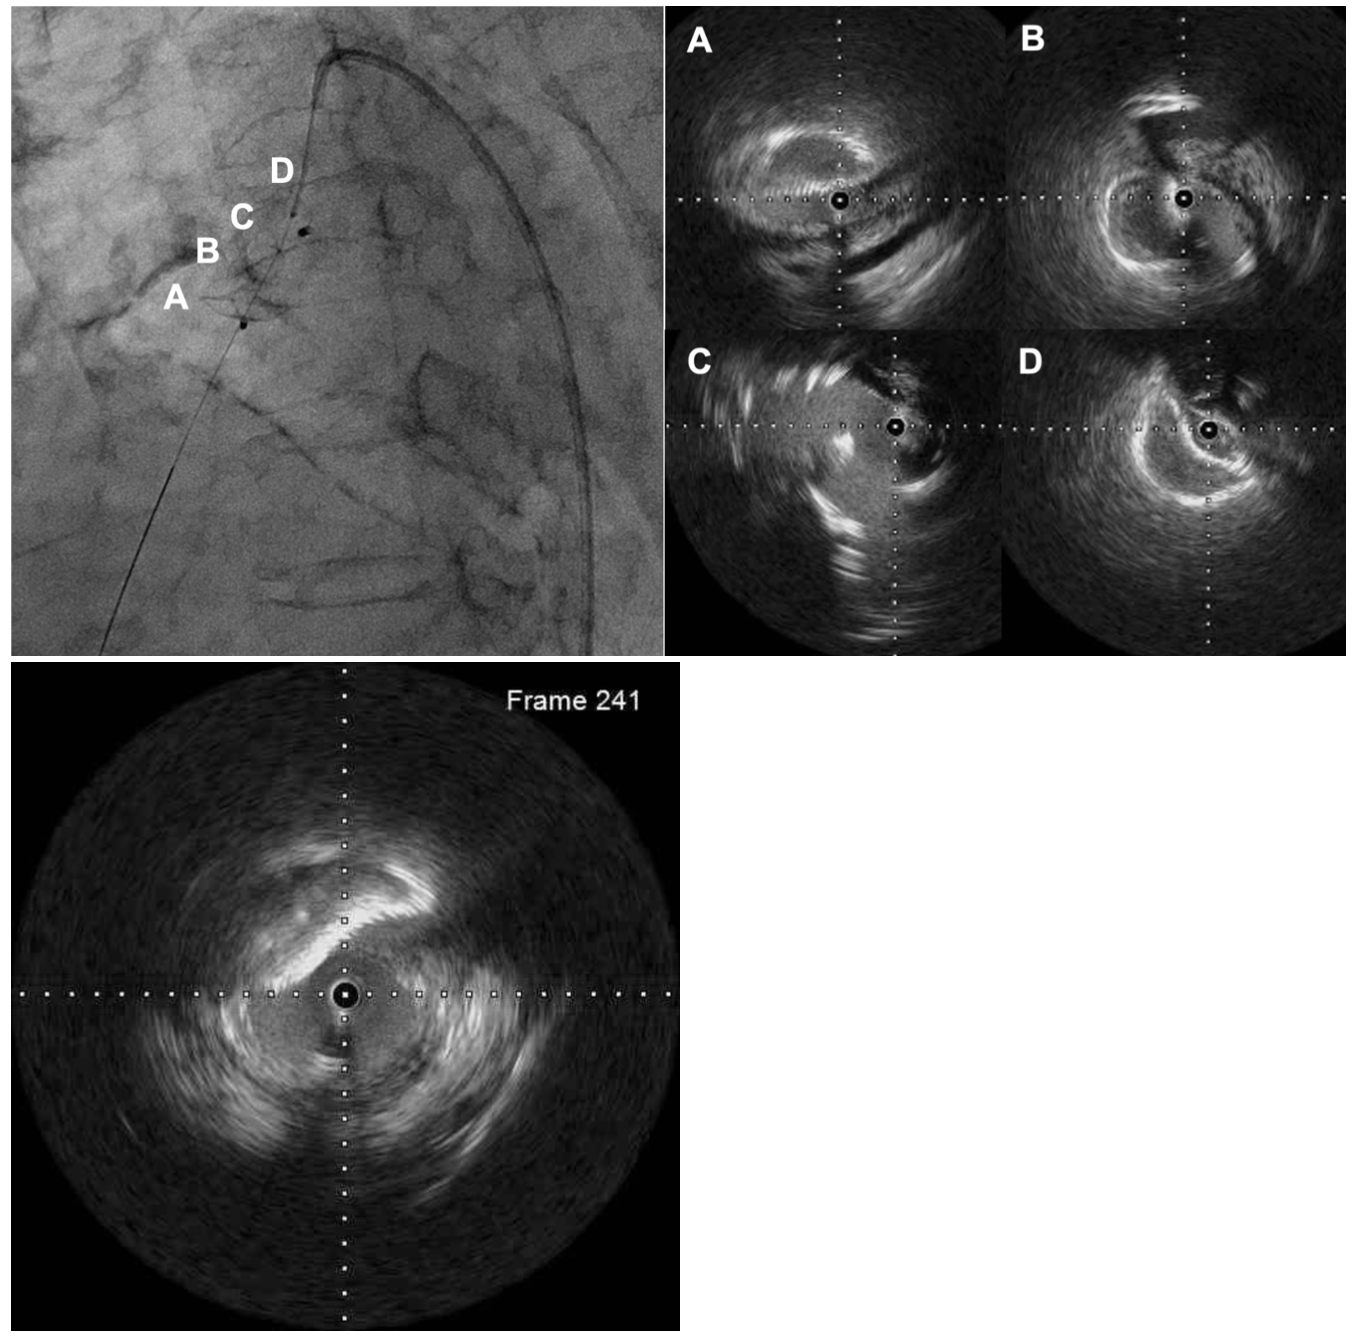

We chose re-intervention for the residual shunt. Intravascular ultrasound revealed that an incomplete closed space outside the ADO II caused the residual shunt (Figure 3, Video 2). We concluded that the ADO II device was over-stretched and not well-positioned due to severe calcification of the PDA. An Amplatzer Vascular Plug II (AVP II) (Abbott) 14/10 was deployed in the space (Figure 4, Video 3), and the PDA flow disappeared completely.